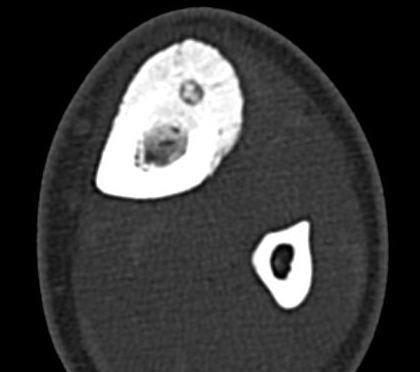

CT

Best investigation

- lucent nidus surrounded by dense bone

Osteoid osteoma tibia